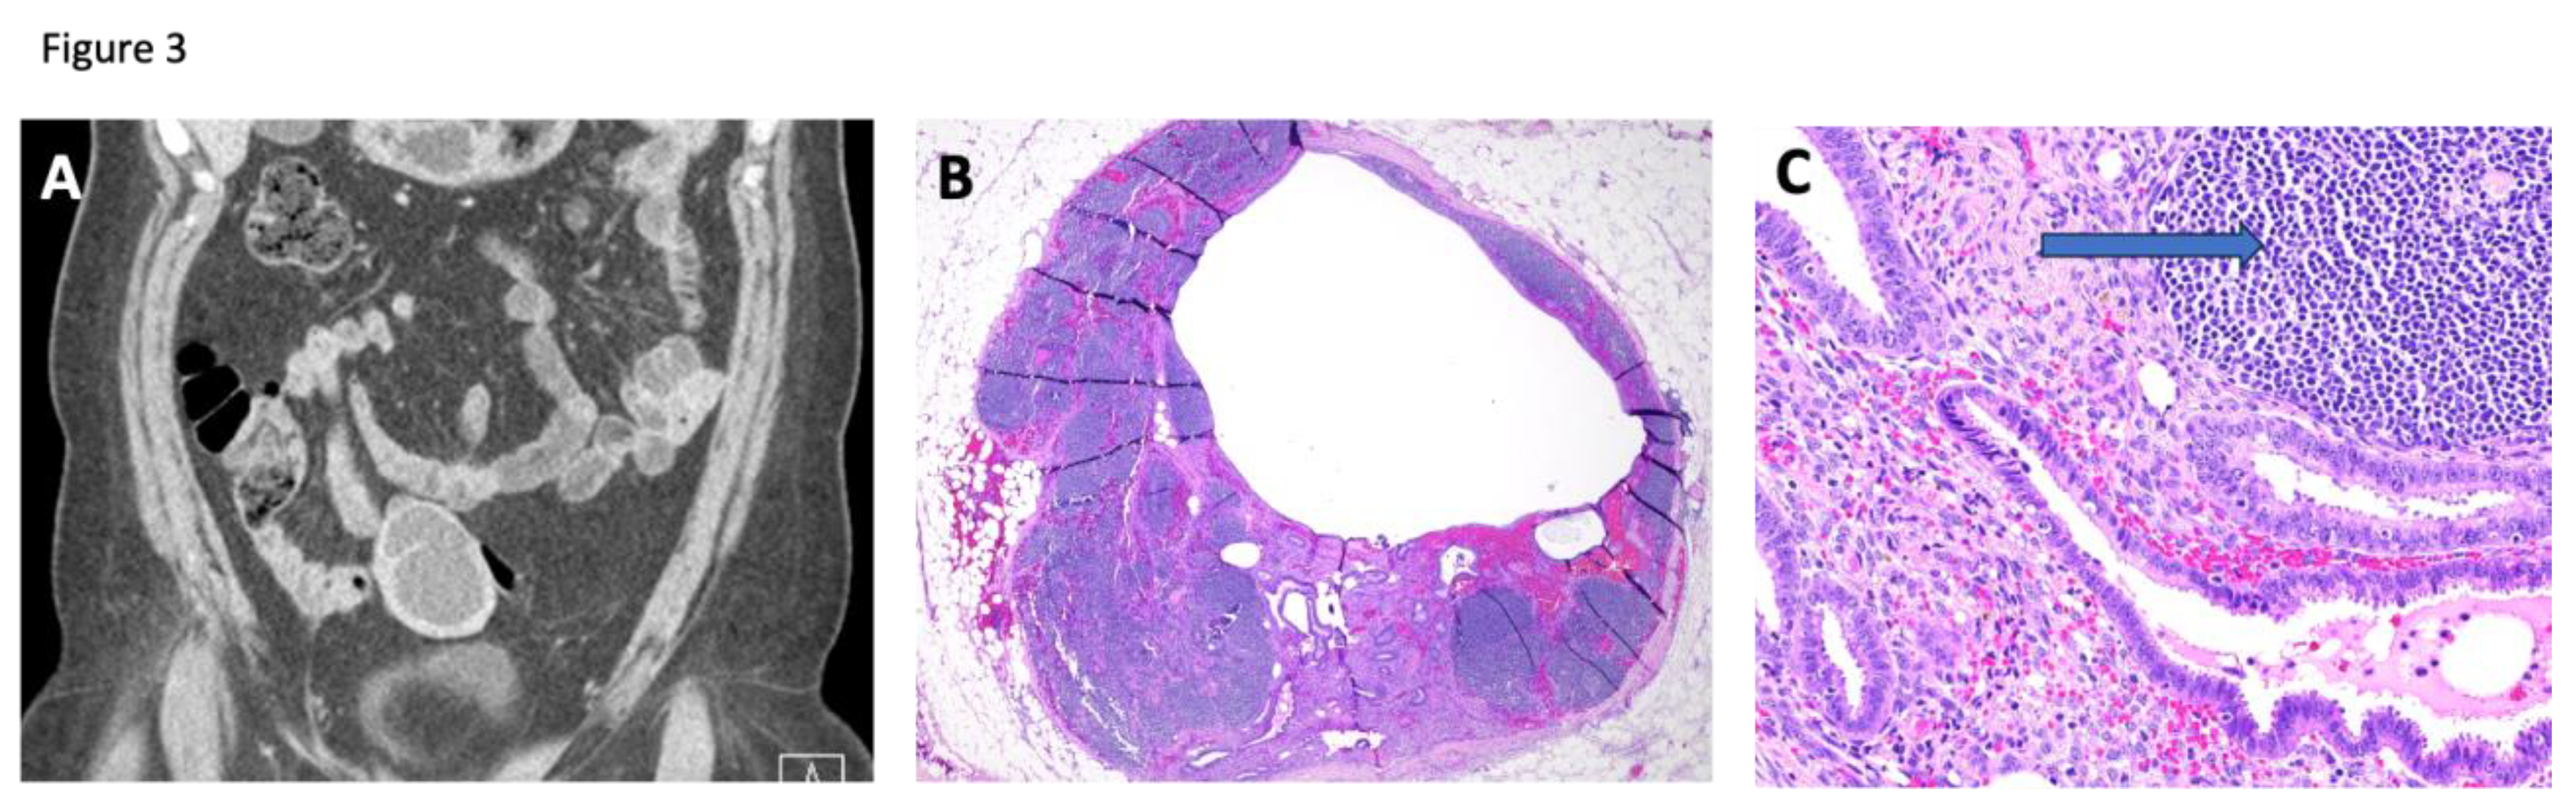

Case 4, a 49-year-old woman, developed a right-sided ovarian mass and left ureteral obstruction requiring percutaneous nephrostomy. Her abdomen and pelvis CT scans showed a right ovarian lesion with suspicious features concerning for neoplastic disease. Pathologic analysis revealed a right endometriotic ovarian cyst and evidence of endometriosis within an enlarged and engorged left pelvic sidewall lymph node and a portion of the sigmoid colon. These samples also demonstrated evidence of adenomyosis. The imaging and pathology of the involved lymph node are shown in Figure 3. Because lymph node endometriosis is less common, we examined its epithelium and found no cancer driver mutations.

Figure 3. An endometriotic lesion found in a bowel lymph node, forming an enlarged pelvic mass in case 4. A: Computed tomography scan shows an enlarged lymph node near the colon. B: Hematoxylin and eosin-stained section at low power (4X) reveals dilated endometrial glands enlarging this lymph node. C: Hematoxylin and eosin-stained section at higher power (20X) displays endometrial glands surrounded by stromal cells. A lymphoid follicle (arrow) is adjacent to the endometriotic tissue.